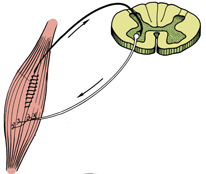

-Əzələ təqəllüsünün izometrik, izotonik formaları, konsentrik və exçentrik hərəkətlər,

postizometrik relaksasiya, gərmə (passiv, aktiv) kimi bütün komponentlərdən

yerinə uyğun kombinasiyaların tətbiq edilməsi;